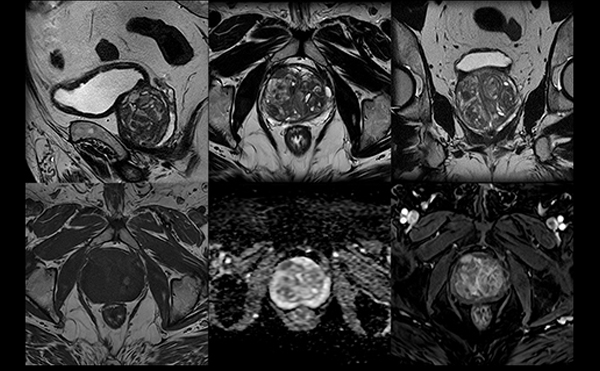

Magnētiskās rezonanses (MR) izmeklējums prostatai tiek veikts, lai detalizēti izvērtētu prostatas struktūru un patoloģiskas izmaiņas.

PI-RADS ir sistēma, ko radiologi izmanto, lai novērtētu prostatas MR attēlos redzamās izmaiņas un noteiktu, cik lielā mērā tās varētu būt saistītas ar prostatas vēzi.

PI-RADS vērtējums tiek izteikts ar ciparu no 1 līdz 5:

• PI-RADS 1–2 nozīmē, ka ļaundabīga procesa iespējamība ir ļoti zema,

• PI-RADS 3 – neskaidra atrade,

• PI-RADS 4–5 – paaugstināta iespējamība, ka atradums varētu būt vēzis.

Svarīgi saprast, ka PI-RADS vērtējums pats par sevi nav diagnoze – tas tikai norāda, cik liels ir ļaundabīga procesa risks. Galīgo apstiprinājumu sniedz biopsija vai histoloģiska analīze.